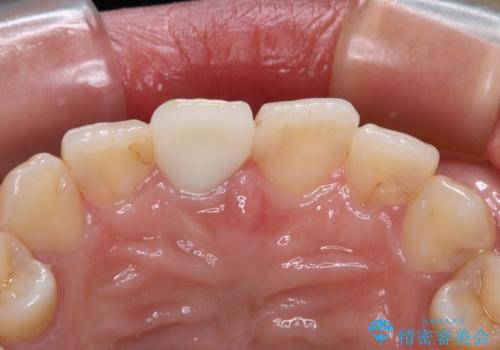

不適合な被せものを除去し、土台の歯の形を修正し、精度の高いシリコーンによる型どりをしました。

色、形ともに自然で嬉しいですと笑顔で言っていただけました。